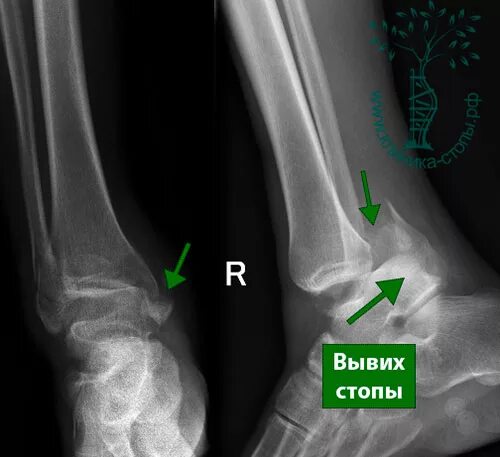

Подвывих сухожилия